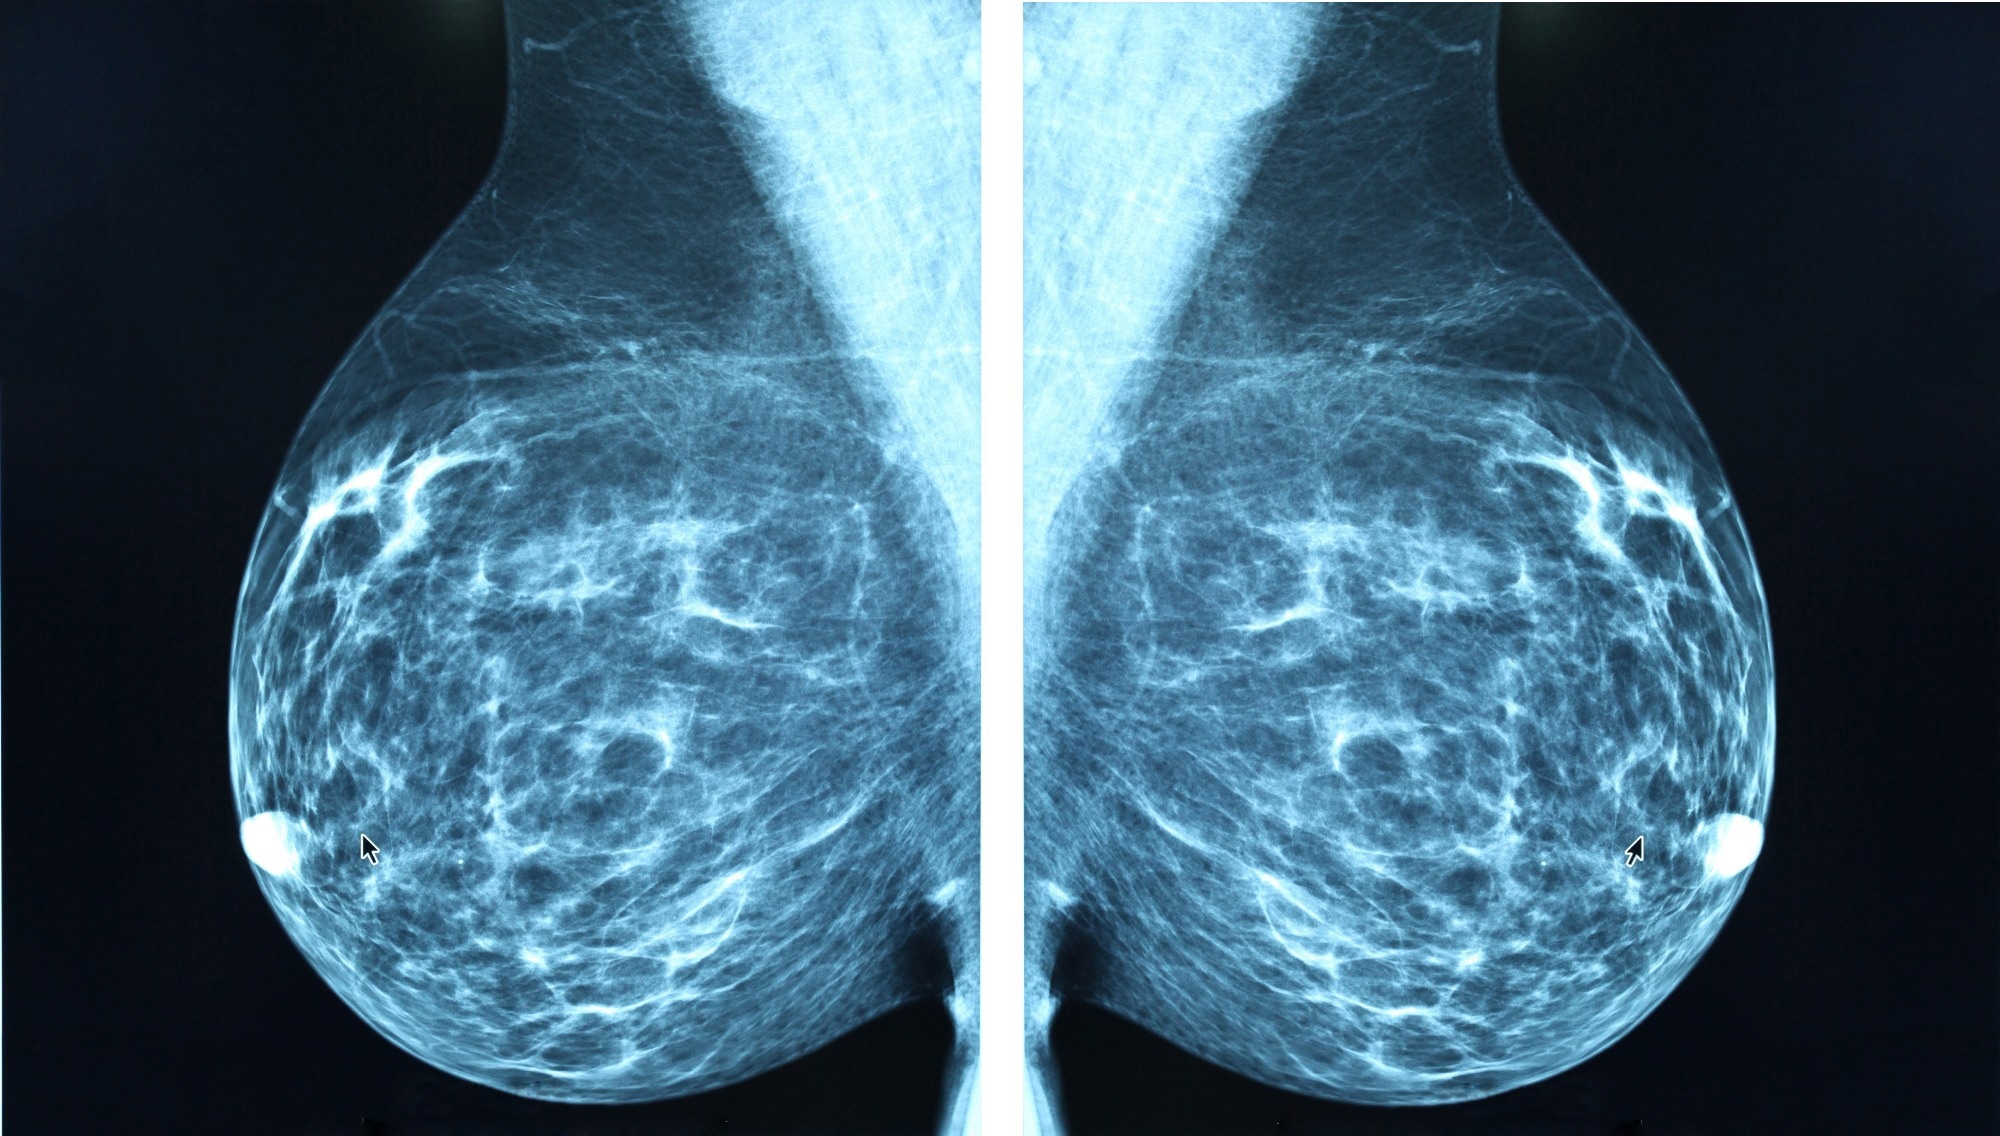

Study: Artificial Intelligence Algorithm for Subclinical Breast Cancer Detection. Image Credit: Blue Planet Earth / ShutterstockStudy: Artificial Intelligence Algorithm for Subclinical Breast Cancer Detection. Image Credit: Blue Planet Earth / Shutterstock